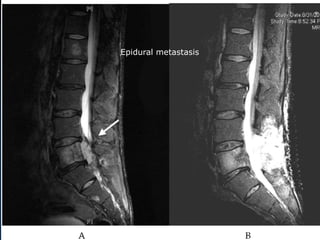

Tumor: vertebral body

 Vertebral body met

Epidural metastasis